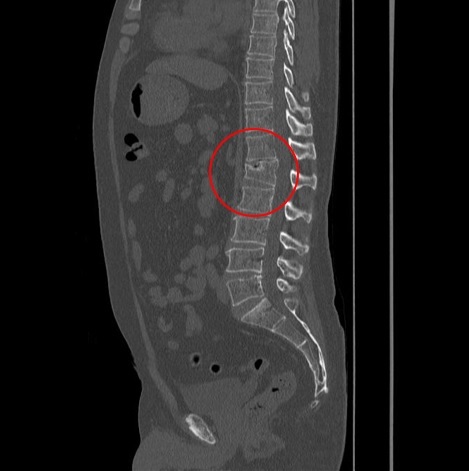

例6 圧迫骨折(腰椎)